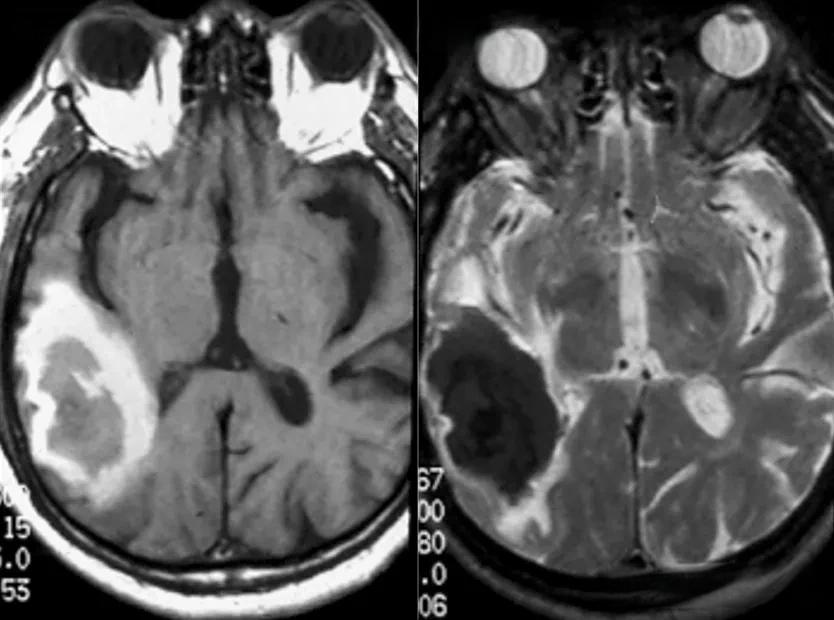

脑出血通常表现为CT图像上的高密度影 ,而MRI则显示为T1加权像上的高信号和T2加权像上的低信号。这种影像特征反映了血液中的铁离子对磁场的干扰。值得注意的是,脑出血的影像表现会随着时间而变化。在超急性期(发病后0-6小时),CT可能无法清晰显示出血灶,而MRI的DWI序列则可以敏感地捕捉到早期出血。

相比之下, 蛛网膜下腔出血的影像学表现更为特异 。CT检查通常能清晰显示脑池、脑沟中的高密度影,而MRI则在T1加权像上显示为高信号。这种影像特征是由于血液中的血红蛋白分解产物与脑脊液混合所致。

值得注意的是,脑梗死的影像表现会随着疾病进程而变化。在急性期(6-24小时),CT开始显示低密度影,而MRI的T2加权像则显示高信号。在亚急性期(24小时-2周),CT上的低密度影变得更加明显,而MRI的T2加权像则显示为高信号。这种动态变化为临床医生提供了重要的诊断线索。